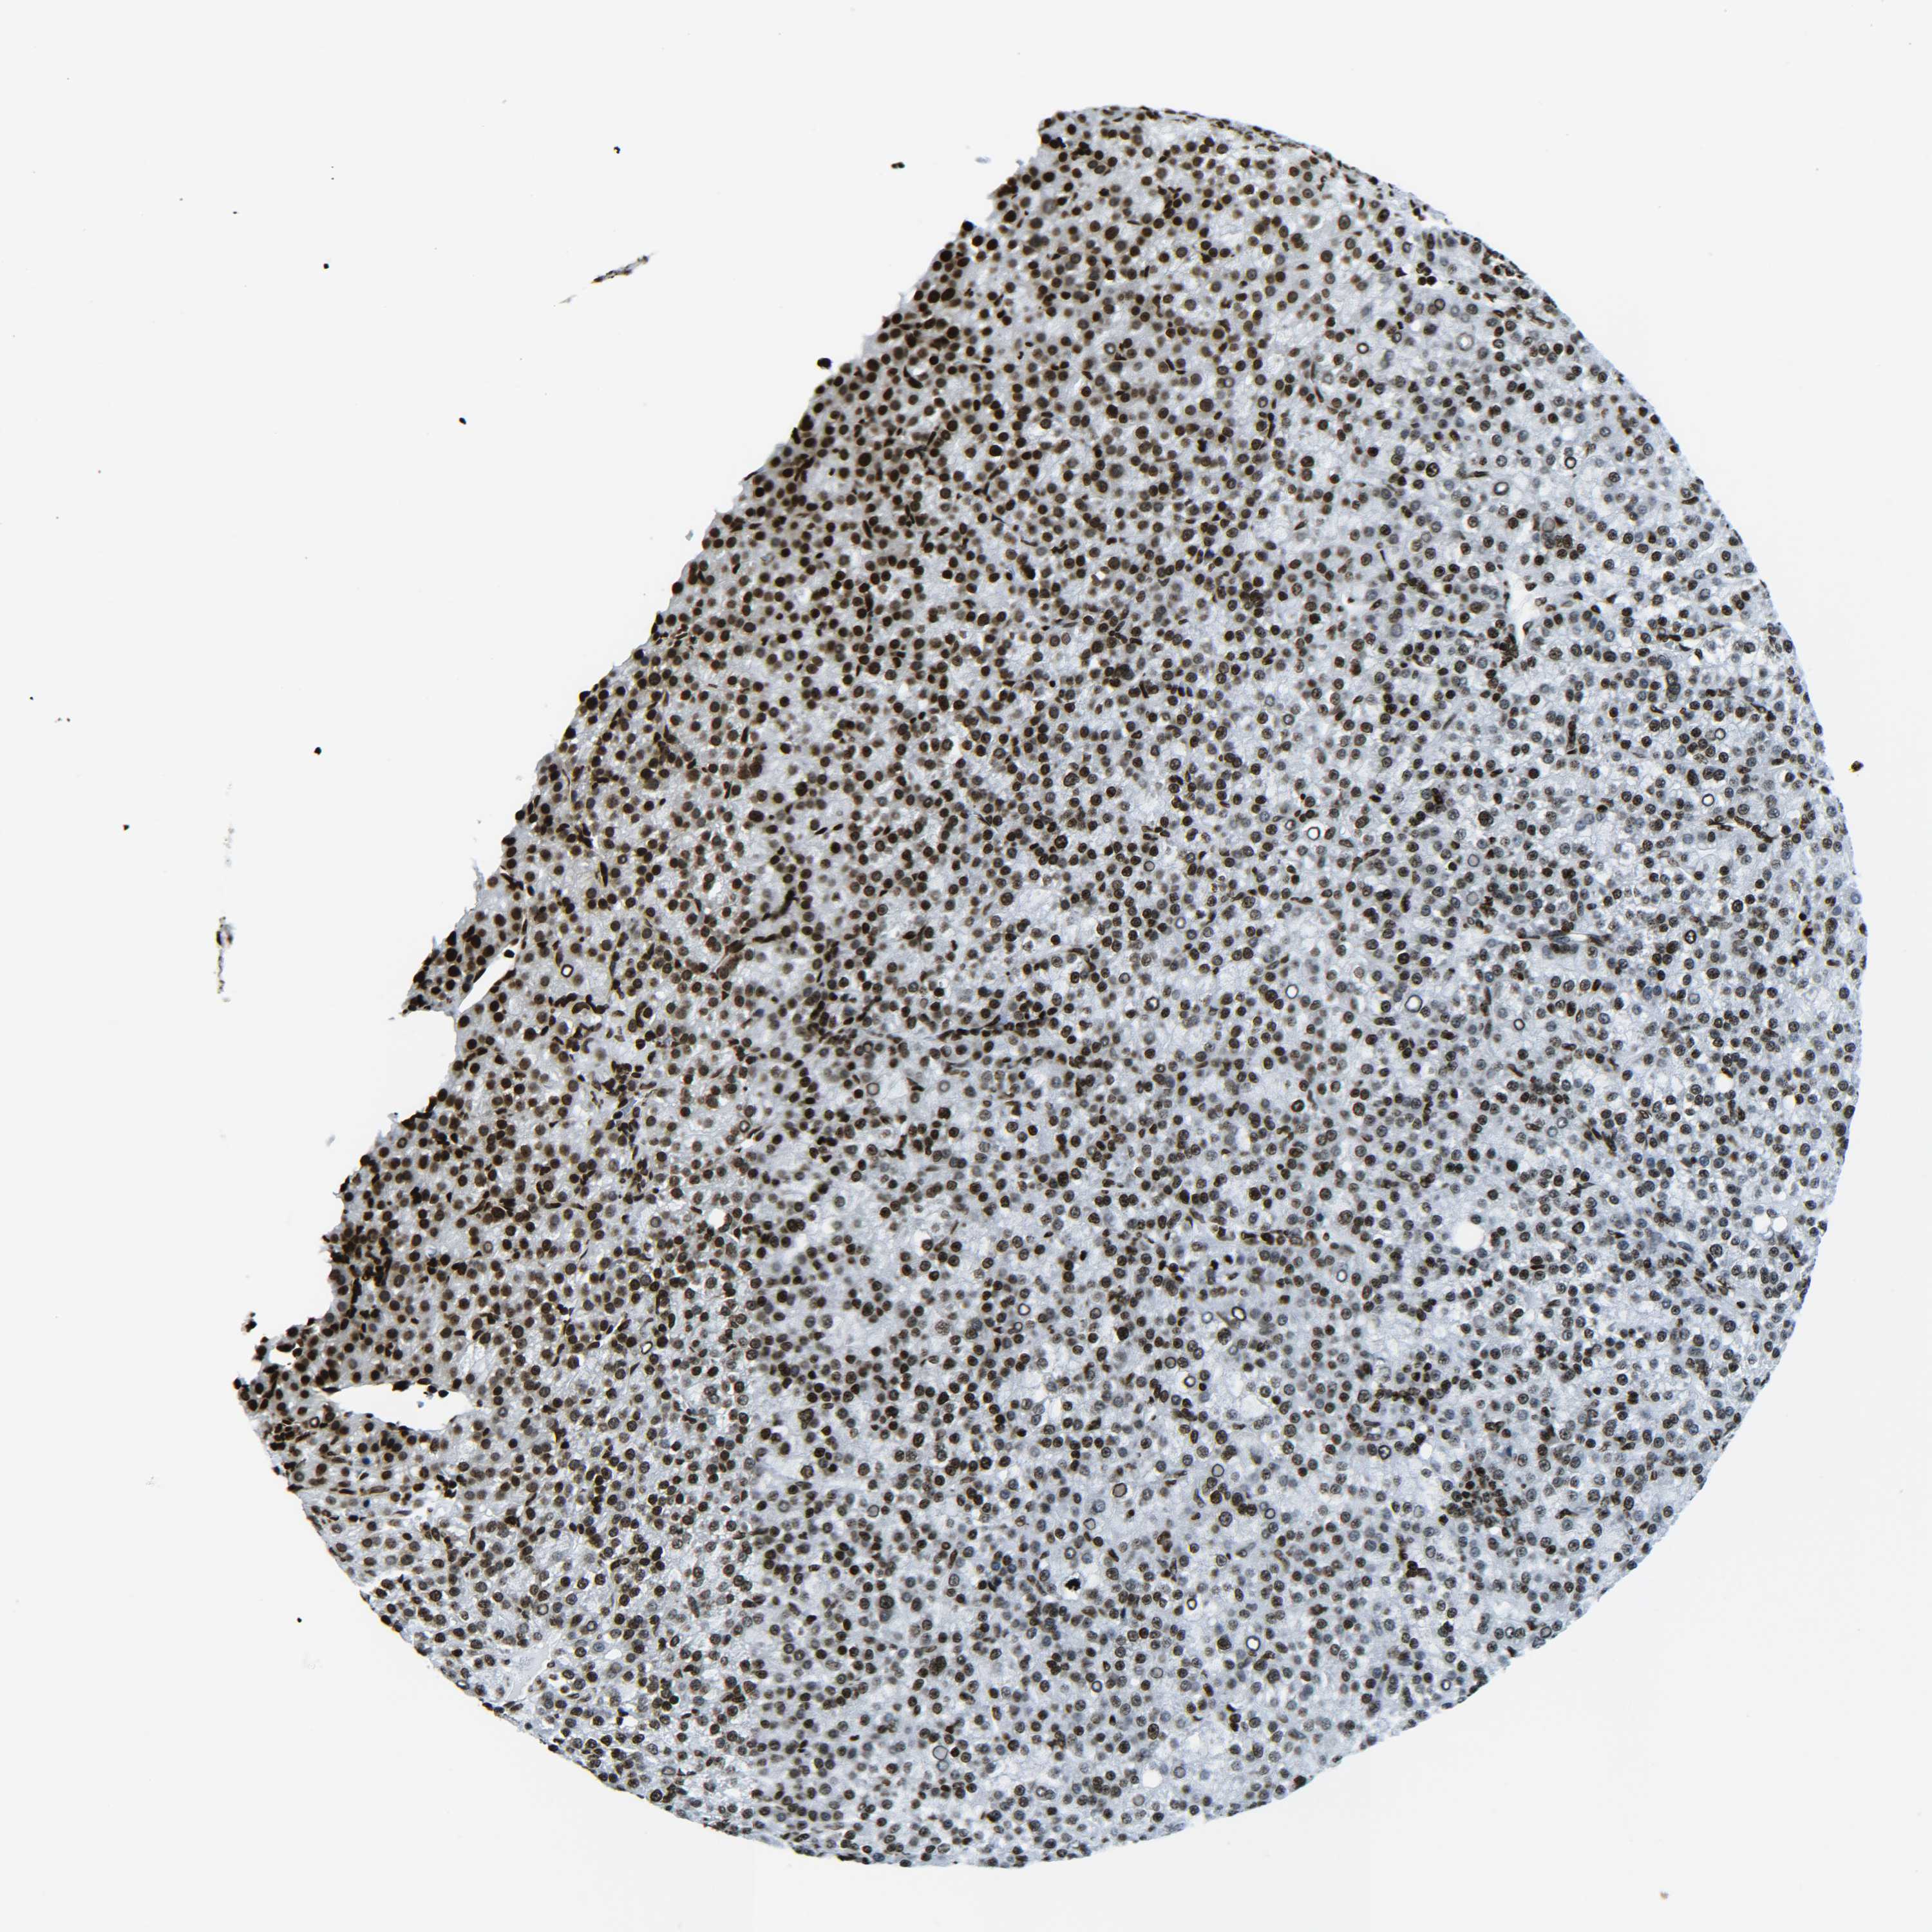

LIVER CANCER - Protein expressioni

A mouse-over function shows sample information and annotation data. Click on an image to view it in a full screen mode. Samples can be filtered based on level of antibody staining by selecting one or several of the following categories: high, medium, low and not detected. The assay and annotation is described here.

Note that samples used for immunohistochemistry by the Human Protein Atlas do not correspond to samples in the TCGA dataset.

Antibody stainingi

Antibody staining in the annotated cell types in the current human tissue is reported as not detected, low, medium, or high, based on conventional immunohistochemistry profiling in selected tissues. This score is based on the combination of the staining intensity and fraction of stained cells.

Each image is clickable and will lead to virtual microscopy that enables deeper exploration of all samples and also displays staining intensity scores, fraction scores and subcellular localization as well as patient and tissue information for each sample.

Antibody HPA041189

Antibody HPA051647

Antibody CAB012264

Staining

High

Medium

Low

Not detected

Intensity

Strong

Moderate

Weak

Negative

Quantity

>75%

75%-25%

<25%

None

Location

Nuclear

Cytoplasmic/membranous

Cytoplasmic/membranous,nuclear

Cholangiocarcinoma

Carcinoma, Hepatocellular, NOS